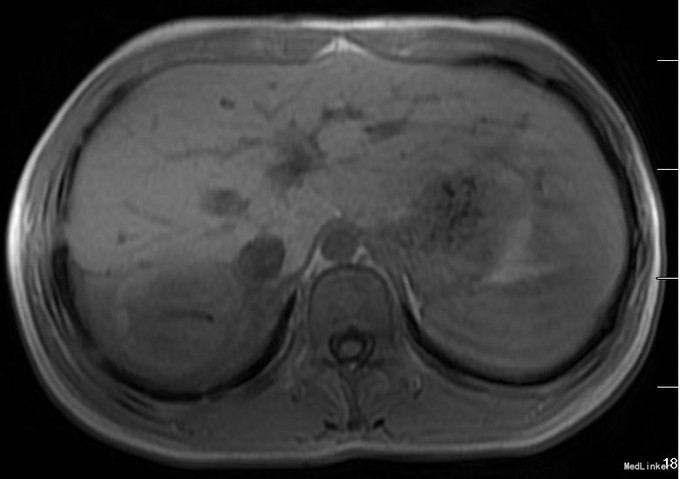

患者术前CT因为外院检查,未得以资料。介入术后17天复查CT(图1):可见引流管留置,肝右后叶占位,6*4cm,实性为主。术后2个月行肝脏增强CT复查(图2):肝右后叶病变,液性区域不多。术后5个月再次行MRI(图3):肝右后叶占位,实性部分占大部分,且与其他肝脏各段似有分界。考虑穿刺引流不能达到消除病灶。行外科手术治疗。手术方案为:肝部分切除,完整切除占位(图4)送冰冻病理回报:炎性假瘤,伴肉芽肿病变。术后患者恢复良好,出院。石蜡病理:考虑结核。